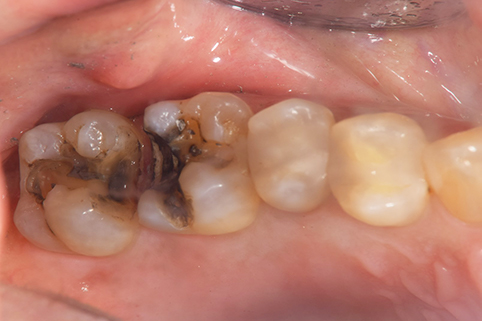

治療前

途中経過

治療後

年齢・性別 43代・女性

主訴 パラジウムインレー2次カリエスの治療

治療内容 左上6セラミックインレー・

左上7ゴールドインレー

治療期間 10日程度

リスク・副作用 虫歯が深ければ、つけた後しみたり、痛みが出る可能性がある。 その場合は神経をとる処置をする。

歯ぎしり、くいしばりでセラミックインレーが割れることがある。

費用 セラミックインレー 55,000円

ゴールドインレー 88,000円